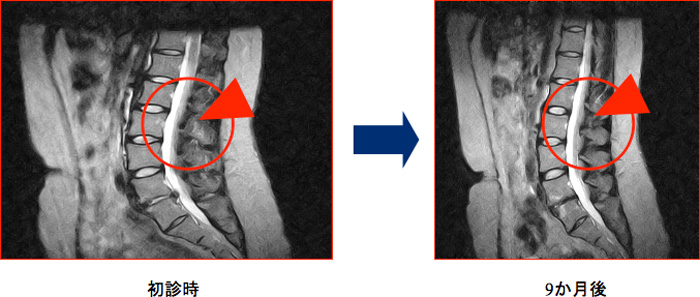

椎間板ヘルニア消失例

脊柱管に脱出したヘルニア腫瘤は、貪食細胞(組織球)によって貪食されて、自然に縮小や消失する場合があります。